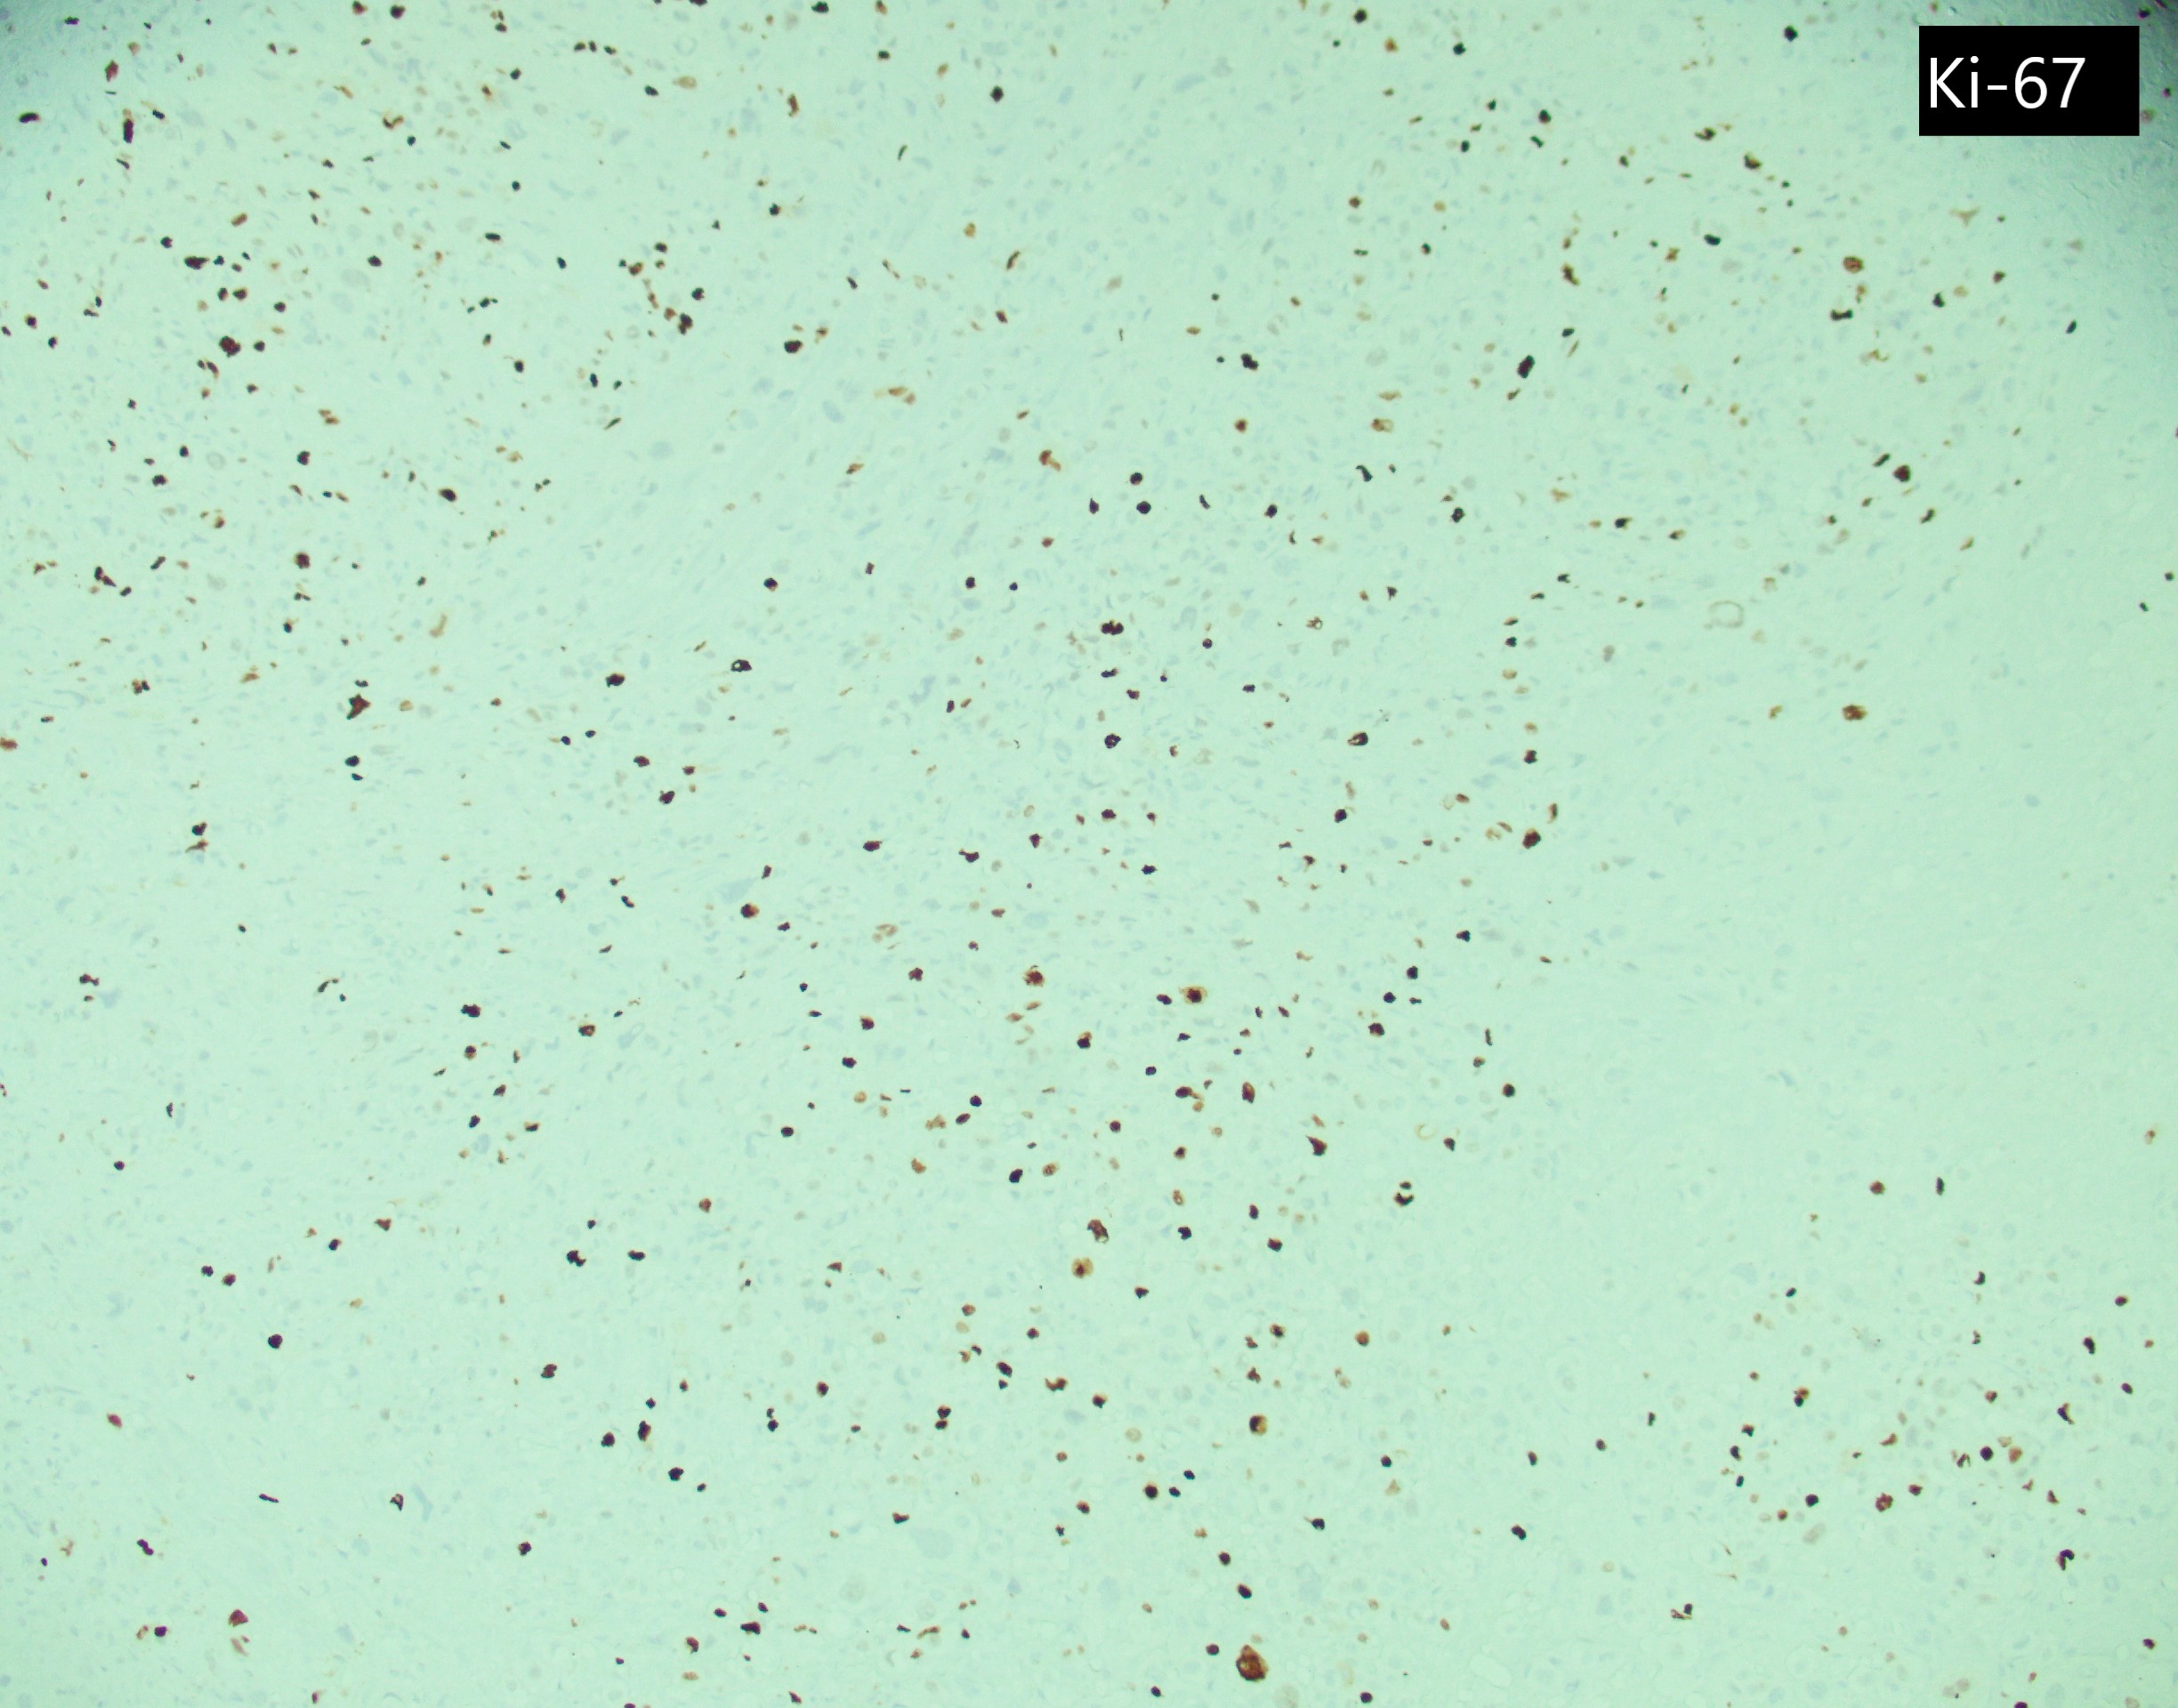

A 19-year-old female with a pregnancy c/b pre-eclampsia. She has had persistent bleeding for 4 months since her delivery. U/S showed a 5 cm endomyometrial mass. Her serum HCG was 161 mIU/mL. D&C showed neoplastic cells which are GATA3+, p63-, and has a Ki67 PI of 30%.

Top differential diagnosis include exaggerated placental site (EPS), epithelioid trophoblastic tumor (ETT) and gestational choriocarcinoma. EPS would show Ki67 proliferation index 1-5%. ETT has similar histologic features on H&E but stains diffuse positive for p63. Gestational choriocarcinoma would show a Ki67 proliferation index >90%.